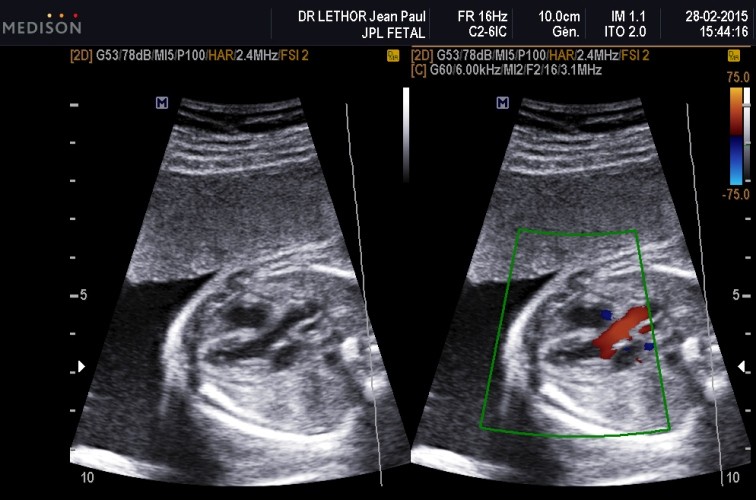

Le Dr. Jean-Paul Lethor est cardiopédiatre, spécialisé dans les malformations cardiaques congénitales.

En Cardiologie Foetale, une malformation ou un trouble du rythme peuvent être détectés en échocardiographie chez le foetus dès la douzième semaine d’aménorrhée (12 SA). Mais le diagnostic précis est fait au mieux après 20 SA.